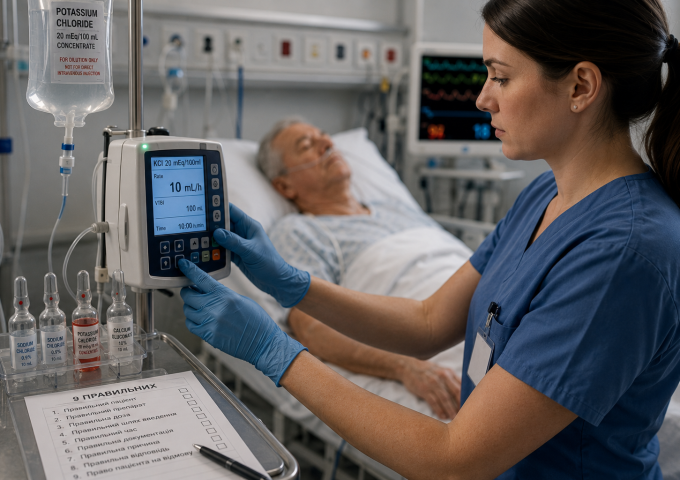

Медсестра поспішала і взяла ампулу концентрованого калію хлориду замість фізіологічного розчину через схоже розташування на полиці. Препарат введено болюсно внутрішньовенно....

Медсестра запрограмувала інфузомат на 15 мл/год для дофаміну, не розраховуючи — «приблизно так зазвичай ставлять». Випадково цифра збіглася з правильною....